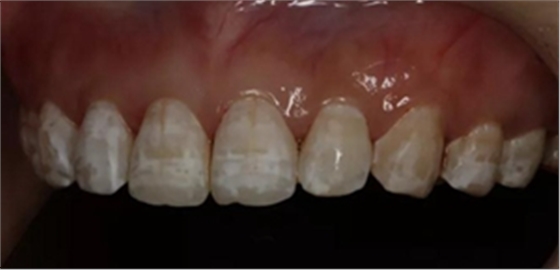

1,術前照片,全口氟斑牙,前牙表面釉質白堊色+黃色斑點+凹坑缺損。

術前正面?zhèn)让嬲掌?/span>